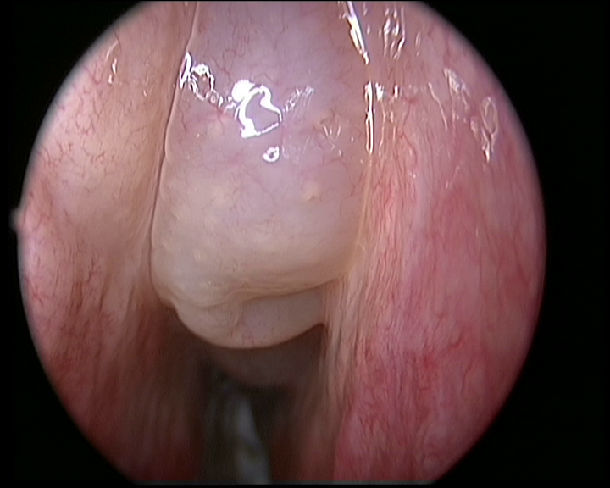

鼻息肉圖片

A:鼻息肉是鼻竇炎的一種,鼻黏膜長期的劇烈水腫、增厚,會形成息肉樣的改變,最終成為息肉。鼻息肉的主要症狀就是鼻子堵塞、不通氣、流鼻涕,特別是膿性鼻涕,嗅覺下降、頭疼等一系列的症狀,檢查時可以看到鼻腔有半透明狀的蒼白樣腫物。如果鼻息肉不能得到及時……

A:有的患者鼻子不舒服而自己看鼻孔,可能會誤把正常的鼻甲或者腫大的鼻甲當成鼻息肉。鼻息肉的形態可以見於一側鼻腔或者兩側鼻腔,灰白色、半透明,像荔枝肉一樣光滑的增生物。鼻甲顏色比較深,質地也比較硬。鼻息肉的症狀往往會引起一側或者兩側的鼻子堵,可……

A:鼻息肉的表現最常見的就是鼻堵,因為鼻息肉如果長的比較大,病人會有鼻子堵的感覺。還有鼻息肉的病人多數會伴有過敏性鼻炎,所以病人會有流鼻涕、打噴嚏、鼻子癢等情況。有了這些情況之後,到醫院就診,通過鼻內鏡檢查,如果鼻息肉比較小,可能會看到鼻腔的中……